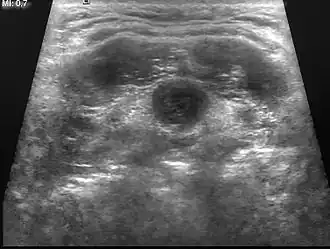

| Echografie | Beeldopname van de grootte van de cyste en de omliggende weefsels. |